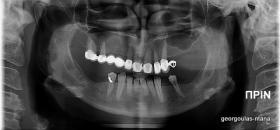

Στην ασθενή αυτή πραγματοποιήθηκε ανοικτή ανύψωση ιγμορείου άνω αριστερά. Σε πρώτη φάση πραγματοποιήθηκε η οστική αύξηση και 6 μήνες μετά τοποθετήθηκαν 3 εμφυτεύματα. Τόσο στην πανοραμική όσο και στην τομογραφία κωνικής δέσμης (CBCT) που πραγματοποιήθηκαν 6 μήνες μετά την ανύψωση είναι εμφανής ο σχηματισμός οστού. Η τελευταία ακτινογραφία και φωτογραφία λήφθηκαν 5 χρόνια μετά την προσθετική αποκατάσταση.